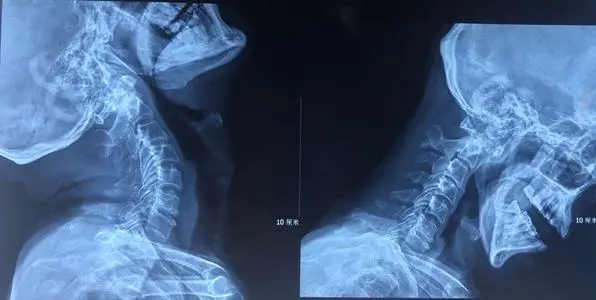

1.2.脊柱X線平片:常見(jiàn)椎弓根破壞、變薄及變形;椎弓根間距增寬,椎間孔擴(kuò)大;椎體后緣破壞、凹陷,椎管前后徑增大;椎管內(nèi)出現(xiàn)斑點(diǎn)狀鈣化灶、椎旁腫瘤影等。

1.4.CT和MRI檢查:CT和MRI,特別是MRI是目前診斷脊髓壓迫癥的安全、方便的檢查手段,能準(zhǔn)確地顯示病變所在的節(jié)段,病變與脊髓、硬脊膜的關(guān)系,鄰近蛛網(wǎng)膜下腔、磋脊膜外腔及骨質(zhì)的變化,對(duì)病變的性質(zhì)也可作出初步診斷。